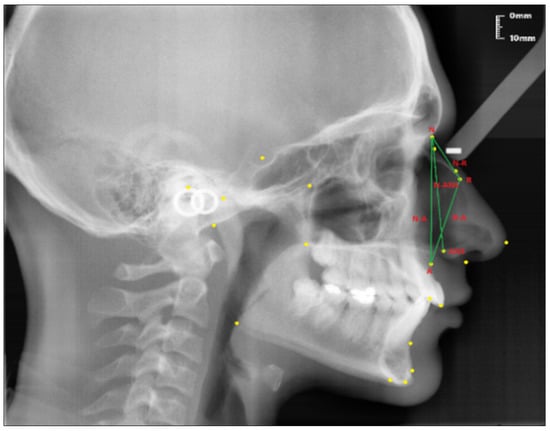

Linear measurements (see Figure 2):

Figure 2.

Linear measurements of the nasal profile used in the study.

- Nasion-Rhinion (N-R); the distance between the nasion and the rhinion points.

- Nasion-Anterior nasal spina (N-ANS); the distance between the nasion and the anterior nasal spina points.

- Rhinion-Subspinale (R-A); the distance between the rhinion and the subspinale points.

- Nasion-Subspinale (N-A); the distance between the nasion and the subspinale points.

Angular measurement (see Figure 3):

Figure 3.

Angular measurement of the nasal bone used in the study.

- Nasal Bone Concavity Angle (Nbone Angle); the posterior angle formed between the N1-N2 line and the N2-R line.